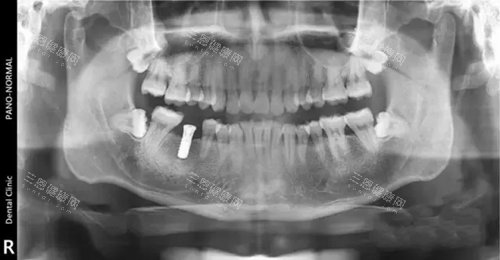

在诊疗过程中,他会特别重视术前检查,比如用口腔CT详细扫描牙槽骨的高度和宽度,确保种植体植入的位置比较准。

有位患者分享,自己缺了一颗后牙,罗医生先做了CT评估,发现牙槽骨有轻微萎缩,建议做小规模骨粉填充后再种植,“整个过程医生会讲清楚每一步要做什么,术后还会发注意事项的文档,很细致”。